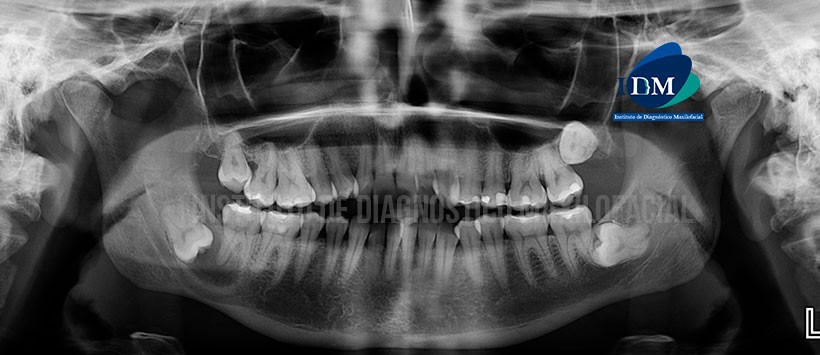

A la evaluación de la radiografía panorámica se aprecia un leve aplanamiento del contorno de ambos cóndilos mandibulares, apiñamiento dentario anterior, múltiples restauraciones, piezas 18 impactadas mesioangulada, la pieza 28 retenida en posición transversa, la piezas  38 impactada en posición horizontal en relación a la cara distal de la piezas  37. Siendo lo mas resaltante la presencia de una imagen radiolúcida de forma redondeada localiza en cuerpo mandibular derecho,  asociado a la pieza 48, que condiciona la perdida de lamina dura la raíz distal de la piezas  47 así como un desplazamiento del conducto dentario inferior hacia la basal mandibular. (Figura 1)